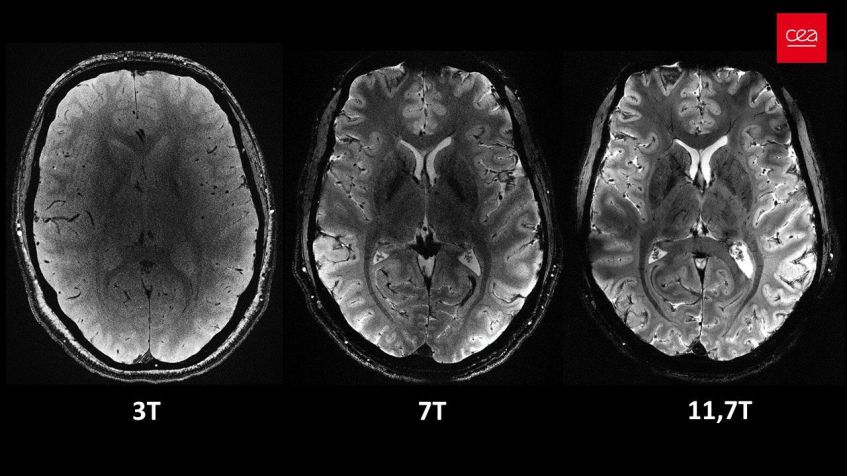

As novas imagens são fruto de mais de 20 anos de pesquisa e desenvolvimento sobre o scanner Iseult, atualmente considerado como o aparelho de ressonância magnética mais poderoso do mundo, possuindo uma intensidade de campo magnético de 11,7 teslas, maior do que aparelhos normalmente utilizados em hospitais, que chegam no máximo a três teslas.